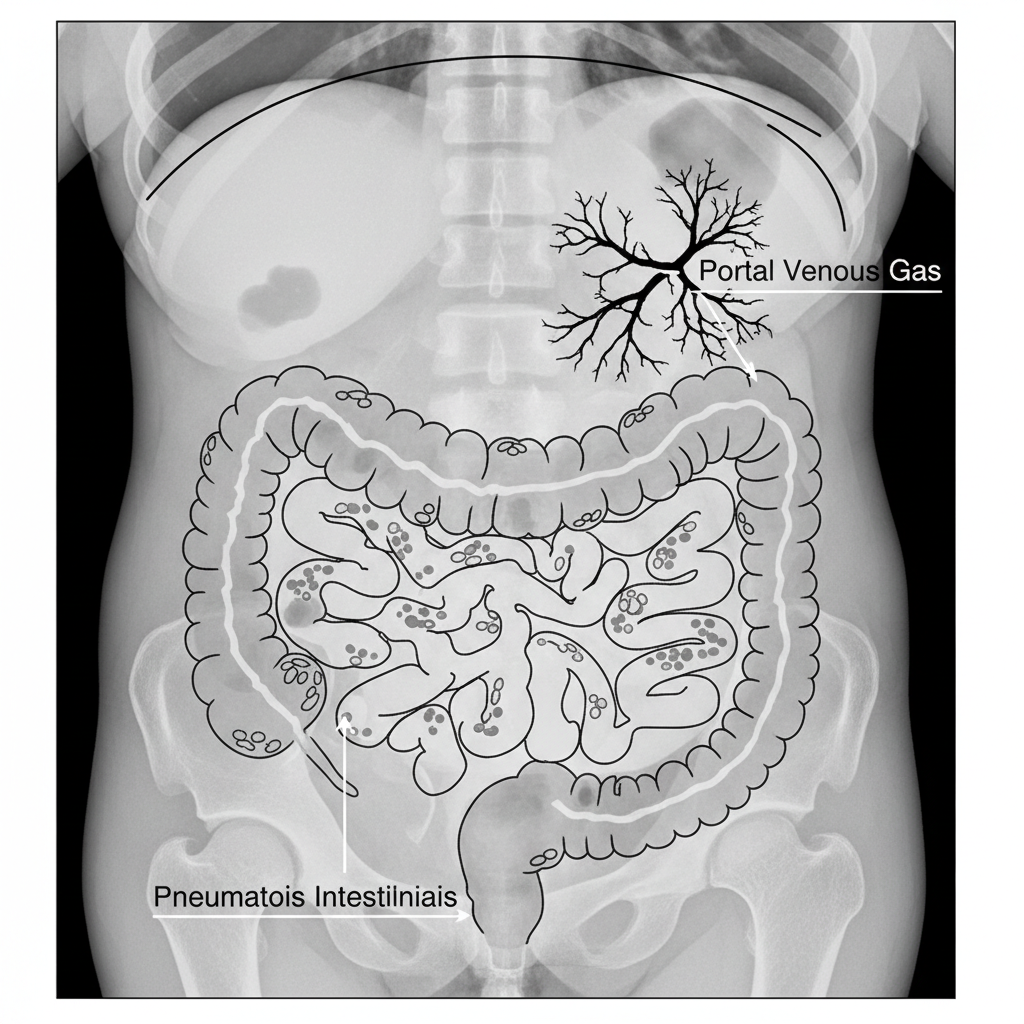

• X-ray: Pneumatosis intestinalis, Portal venous gas.

Key Sign 1: Pneumatosis Intestinalis (air in bowel wall - bubbles/tracks).

Key Sign 2: Portal Venous Gas (branching air over liver).

Labeled schematic drawing of a neonatal abdominal X-ray focusing on Pneumatosis Intestinalis and Portal Venous Gas, high contrast black and white diagram style

• <strong>Schedule:</strong> Serial AP AXR every 6-8 hours in acute phase (Stage I/II).<br>• <strong>Key Sign 1:</strong> Pneumatosis Intestinalis (air in bowel wall - bubbles/tracks).<br>• <strong>Key Sign 2:</strong> Portal Venous Gas (branching air over liver).<br>• <strong>Key Sign 3:</strong> Pneumoperitoneum (Rigler's sign / Football sign).<br>• <strong>Ultrasound:</strong> Recommended for early detection or complex fluid collections.